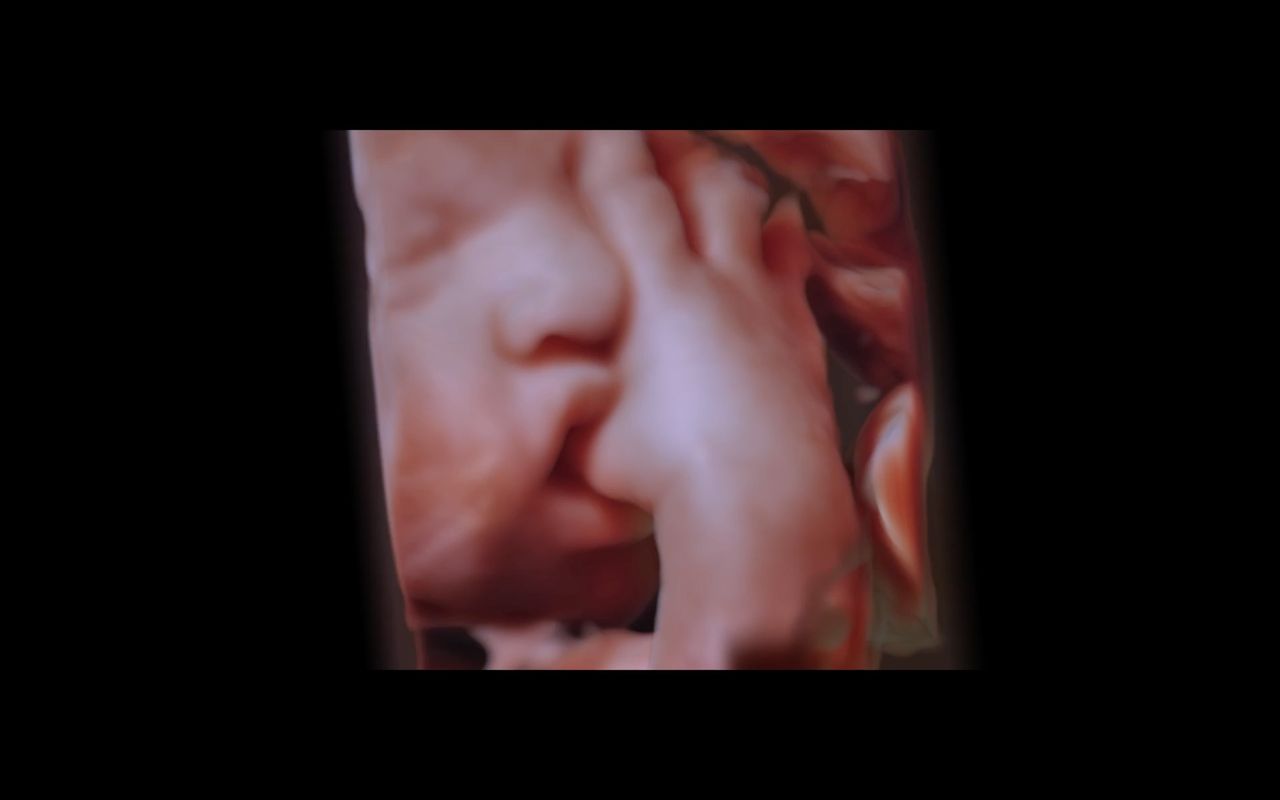

Jestem lekarzem, ginekologiem-położnikiem, absolwentką Collegium Medicum Uniwersytetu Jagiellońskiego w Krakowie. Przez długi czas byłam związana z Katedrą Ginekologii i Położnictwa Uniwersytetu Jagiellońskiego Collegium Medicum w Krakowie jako nauczyciel akademicki. W 2007 roku uzyskałam nostryfikację dyplomu lekarskiego w Stanach Zjednoczonych. Tytuł doktora nauk medycznych uzyskałam na podstawie obronionej rozprawy doktorskiej z zakresu problematyki układu immunologicznego w ciąży pozamacicznej. Praca lekarza jest moją wielką pasją, a moje doświadczenie kliniczne zdobyłam pracując w Oddziale Ginekologii i Onkologii Szpitala Uniwersyteckiego w Krakowie. Jestem doświadczonym specjalistą w zakresie ultrasonografii położniczej, ginekologicznej i onkoginekologicznej, a wszystkie badania wykonuję zgodnie z najnowszymi rekomendacjami Sekcji Ultrasonografii Polskiego Towarzystwa Ginekologicznego, Fetal Medicine Foundation (FMF) oraz The International Society of Ultrasound in Obstetrics and Gynecology (ISUOG). Moje zainteresowania dotyczą również zagadnień dotyczących diagnostyki i leczenia niepłodności oraz metod wspomaganego rozrodu. W trosce o najlepszą opiekę nad Pacjentkami staram się poszerzać moją wiedzę przez uczestnictwo w licznych kursach i kongresach. Będąc lekarzem, a zarazem kobietą mam świadomość jak intymnym przeżyciem jest wizyta u ginekologa, dlatego zwracam uwagę na indywidualne podejście do każdej Pacjentki, tak jak sama chciałabym być leczona będąc Pacjentką.

I am a physician, a gynecologist- obstetrician. I graduated from the Jagiellonian University Medical College. For a long time, I worked as a university teacher at the Department of Gynecology and Obstetrics, Jagiellonian University Medical College. In 2007, my medical doctor’s diploma, which I received in the USA, was officially recognized. My MD-PhD I obtained on the basis of my doctor thesis dealing with the problems concerning the immune system in the ectopic pregnancy. This profession is my passion. I gained my experience working at the Department of Gynecology and Oncology in the Krakow University Hospital. I am an experienced specialist in obstetric, gynecologic and oncologic ultrasound, and all of my examinations are carried out according to the newest recommendations of the Ultrasound Section of the Polish Gynecological Society, Fetal Medicine Foundation (FMF) as well as The International Society of Ultrasound in Obstetrics and Gynecology (ISUOG). My interests also include issues concerning the diagnosis and treatment of infertility and methods of assisted reproduction. Out of concern for my Patients, I constantly try to extend my knowledge through participating in numerous courses and congresses. Being both a doctor and a woman, I am aware of the intimacy of an appointment at a gynecologist, and that is the reason why I pay a special attention to an individual approach to each of my Patients, which is the way I would like to be treated as a Patient. Best regards, Anna Knafel